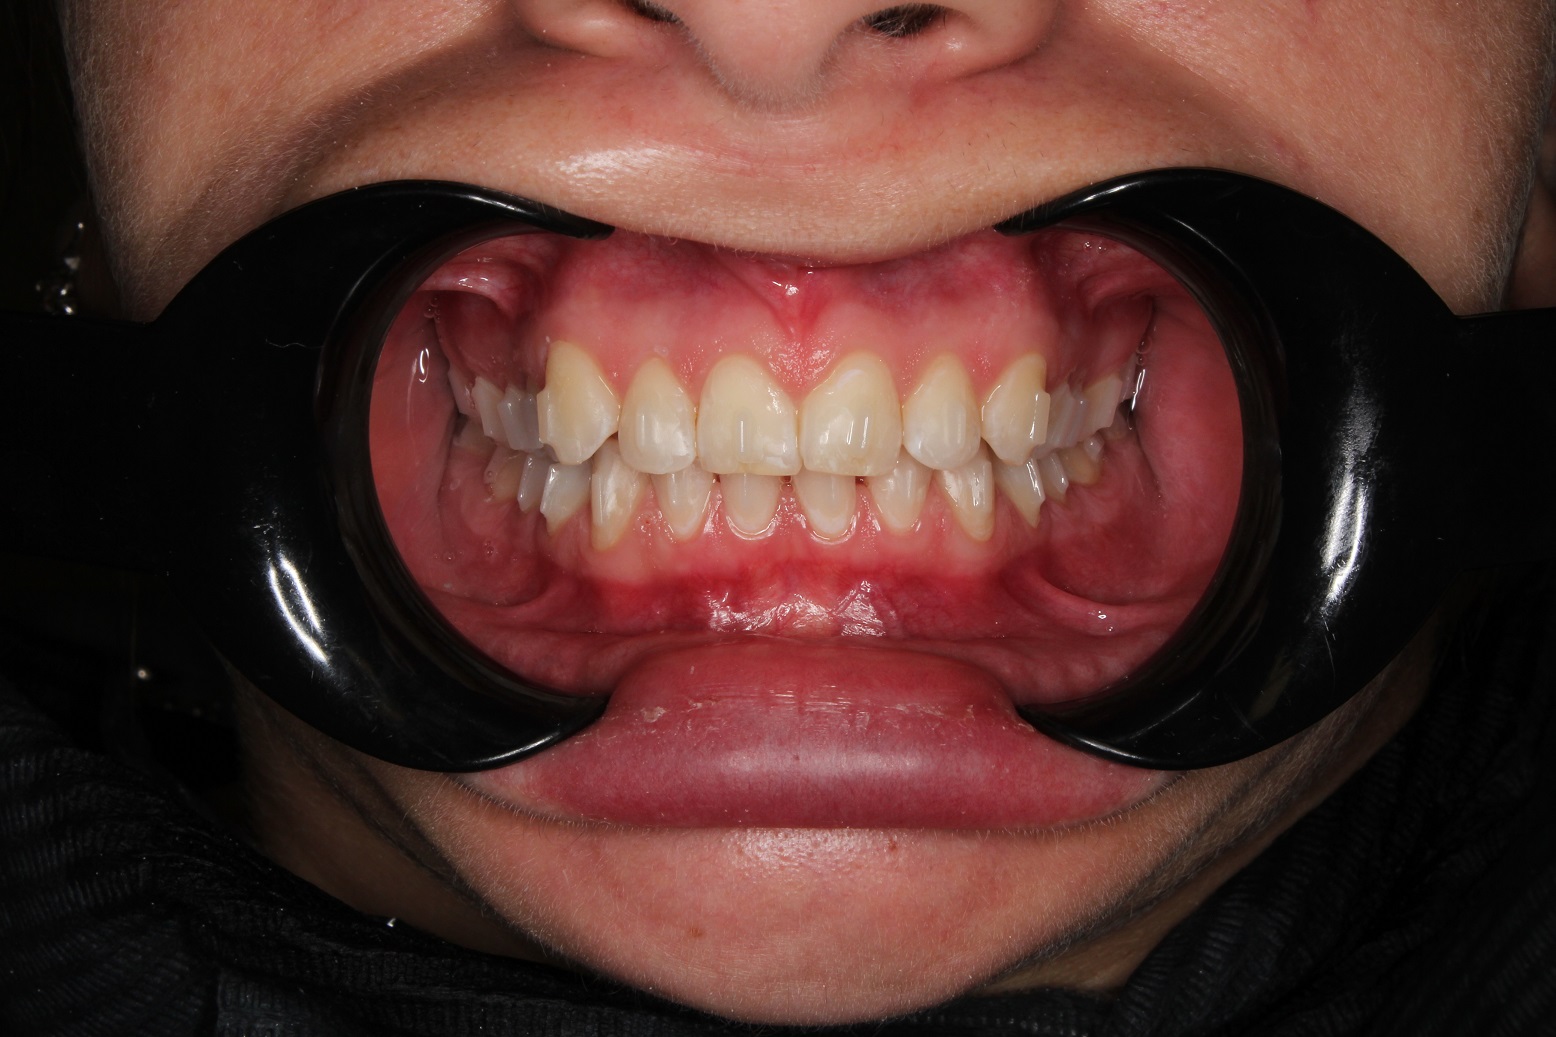

До и После: Лечение глубокого прикуса с помощью элайнеров Eurokappa